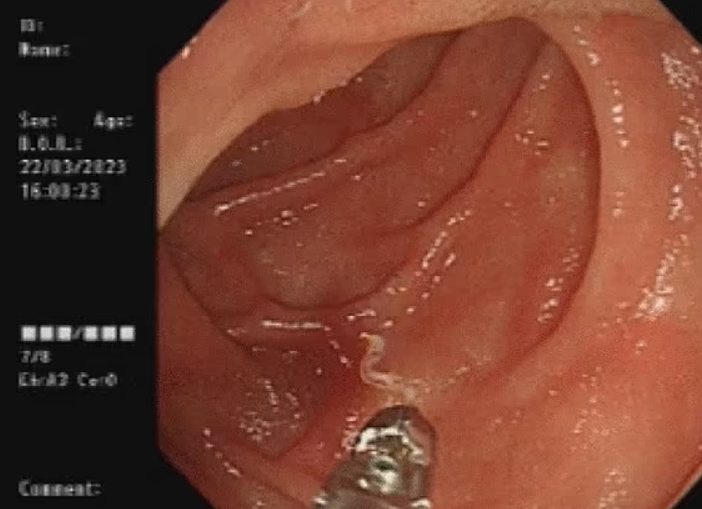

이에 의료진은 내시경 검사를 진행했고, 그 결과 여성의 장에서 살아있는 기생충을 발견했다. 이 기생충은 빈혈을 일으키는 ‘아메리카구충’(Necator americanus)이었다.